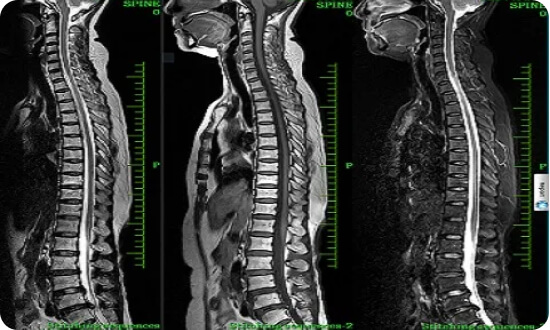

MRI Cột sống

- Hình ảnh cột sổng cổ, ngực, thắt lưng với độ phân giải cực cao

- Giảm nhiễu ảnh do bộ phận cấy ghép kim loại

Ứng dụng nâng cao

- Tái tạo đường cong tự động toàn bộ cột sống

- Chụp đám rối thần kinh